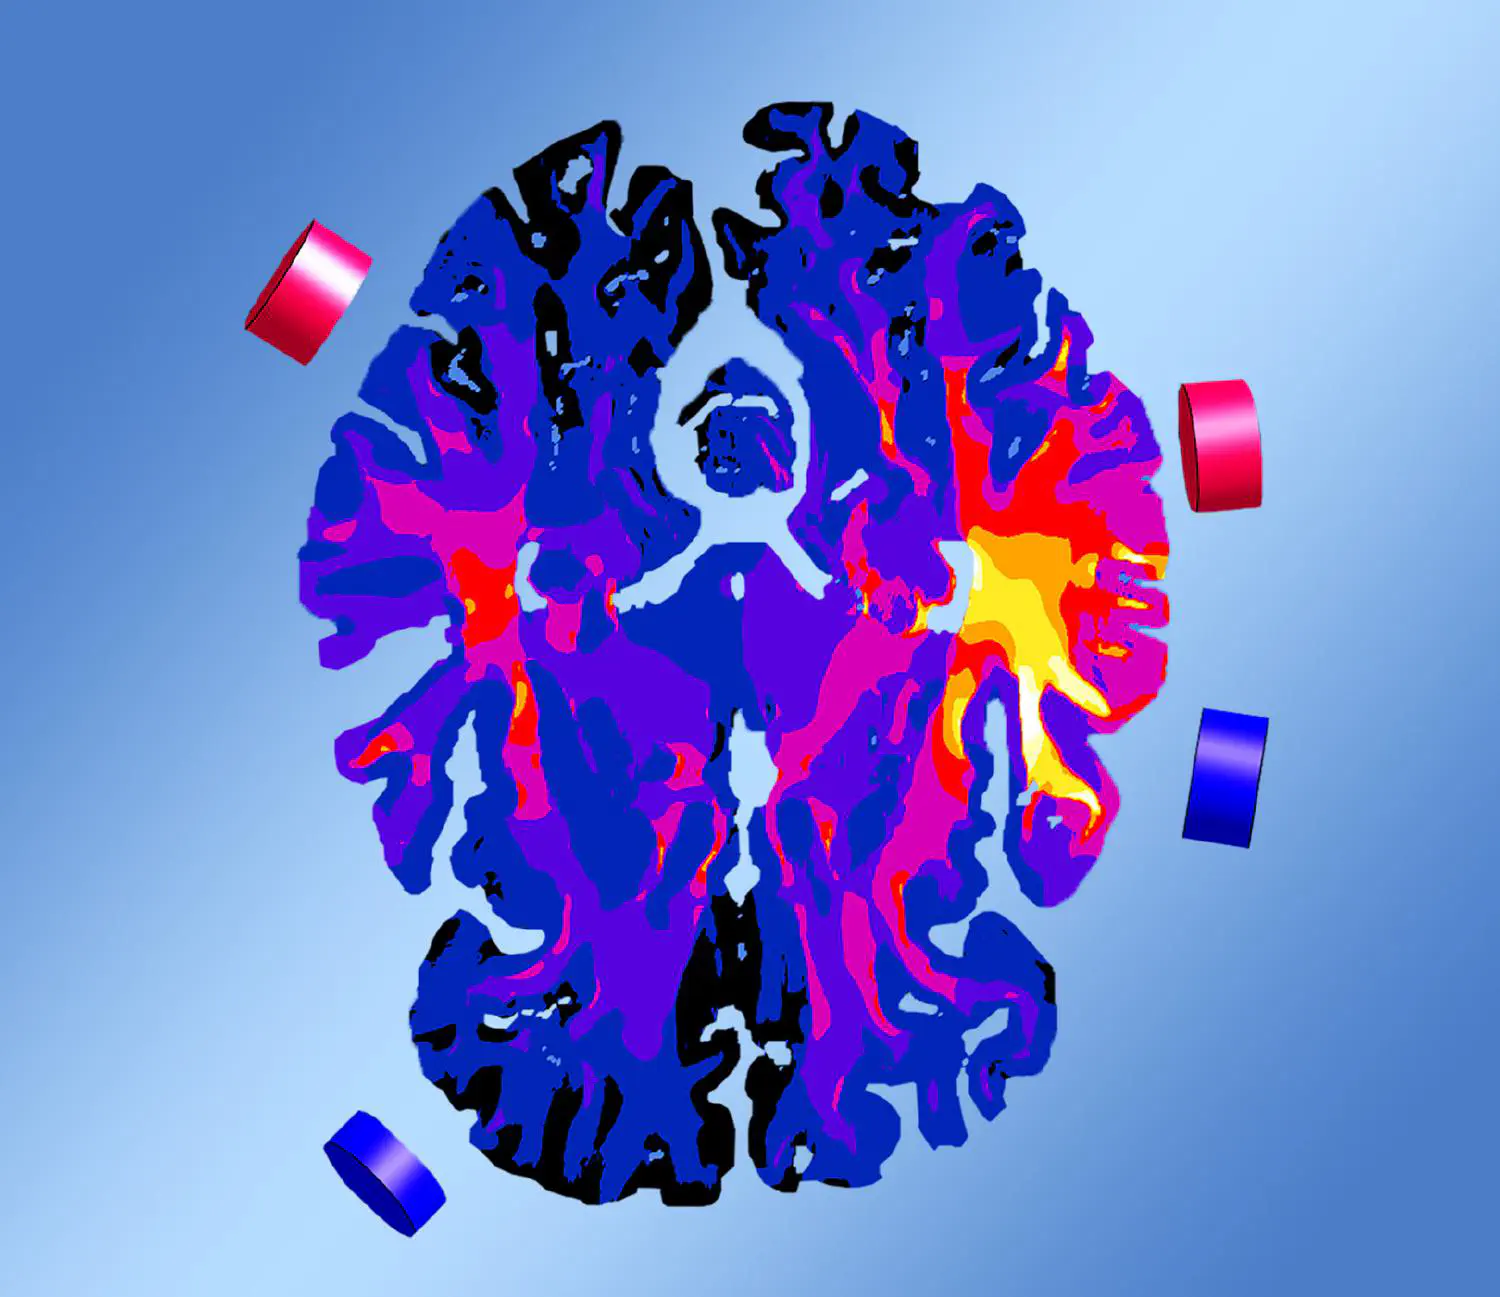

TI introduces a new non-invasive method for sculpting electric fields, enabling, for the first time, steerable, precise deep brain stimulation. This innovation paves the way for targeted, more effective treatments for a wide range of brain disorders.

Temporal interference (TI) bridges the gap between classical NIBS technologies and DBS: it enables non- or minimally invasive, steerable stimulation of deep brain structures. This new method paves the way for a transformative stimulation strategy for a wide range of brain disorders, opening new possibilities for safe, effective, and patient-centered therapies.

Temporal interference (TI) is a new non-invasive brain stimulation method capable of targeting deep brain structures, unlike conventional transcranial electrical stimulation.

TI stimulation utilizes harmonic electric fields applied through scalp electrodes at slightly different frequencies in the kHz range (e.g., f1 = 10.00 kHz and f2 = 10.01 kHz). The difference between these frequencies creates an envelope, also called beat frequency (here: 10 Hz), which falls within the physiological range of brain activity (1 – 100 Hz), and is able to modulate neural activity. This enables targeted stimulation of specific brain regions without affecting nearby areas. Additionally, adjusting the electrical currents across electrode pairs allows for steering, offering flexibility without the need to move the electrodes.